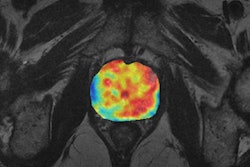

- Francesco Ceci, Italy: Ga-68 PSMA PET/CT for early restaging prostate cancer. Preliminary results of a prospective trial in patients with biochemical failure after radical therapy and PSA levels < 2 ng/mL

- Egesta Lopci, Italy: Prognostic significance of molecular and imaging biomarkers in primary brain tumors